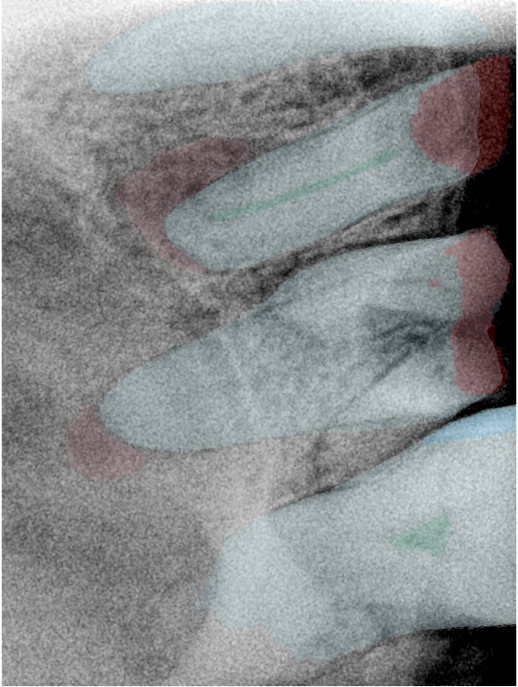

CR/DR 牙齿分割阶段记录

当前进展

- 完成了 CR/DR 牙齿相关分割训练

- 当前结果已经达到阶段预期,但仍有细节问题需要继续处理

相关测试

遇到的问题

- 训练过程中出现过 mask 下移问题

- 部分结果会出现 box 填充异常

- mask 边缘仍然有比较明显的锯齿感